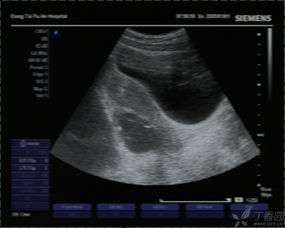

肝膽胰等部位的B超檢查需要空腹,因?yàn)楦文懸任挥谂枨桓共康纳钐?,因此也就特別容易受到消化道氣體的影響,如果不空腹去進(jìn)行檢查就非常容易使結(jié)果產(chǎn)生偏差,從而達(dá)不到檢查的目的。

做B超檢查的時(shí)候是否空腹,主要是看具體是針對(duì)哪一部位的B超檢查,要具體情況具體分析。如果不知道自己做的B超檢查是否要空腹,需要提前就咨詢醫(yī)生,以免耽誤檢查的時(shí)間。